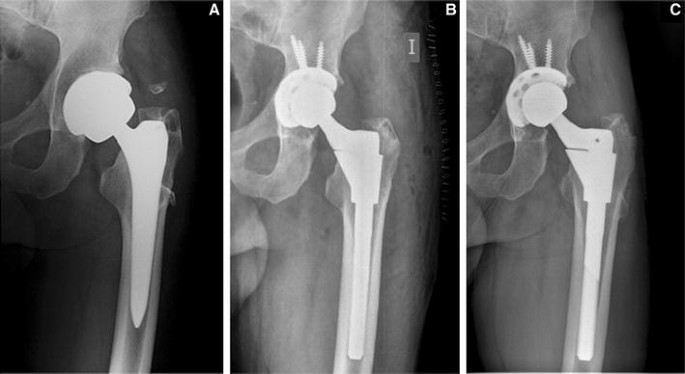

A revision total hip replacement is an operation to take out parts of your old hip replacement and put in new ones.

fracture (break) of the femur around your hip replacement